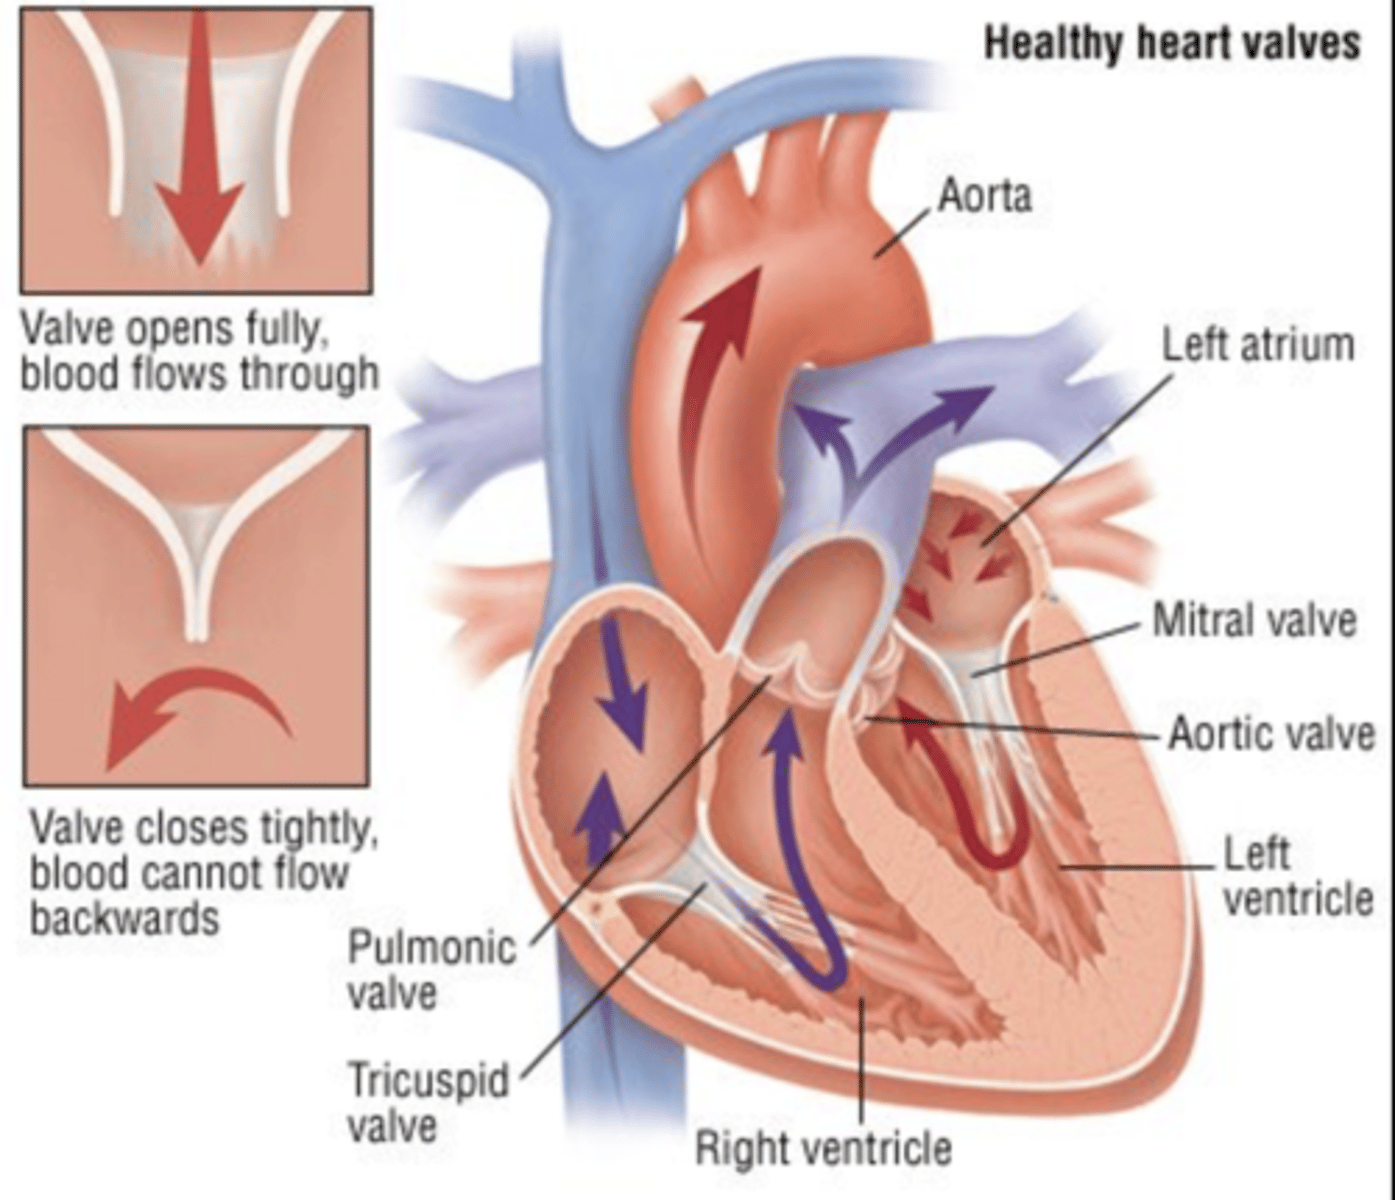

What are the valves separating atrium and ventricle?

. Tricuspid valve (right atrioventricular valve, 3 cusps)

. Mitral or bicuspid valve (left atrioventricular valve, 2 cusps)

What are the four valves in the heart?

Tricuspid

Mitral or bicuspid

Pulmonary

Aortic

What valves are assuring the AV unidirectional flow?

Tricuspid (right)

Mitral or bicuspid (left)

How do the AV valves respond during the cardiac cycle?

AV valves open during diastole

AV valves close in systole

OPEN : ALLOW FLOW FROM ATRIA TO VENTRICLES

CLOSE : PREVENT BACKFLOW

How are the valves open in diastole?

AV valves are open,

Semilunar valves are closed

How are the valves open in systole?

AV valves are closed

Semilunar valves are open